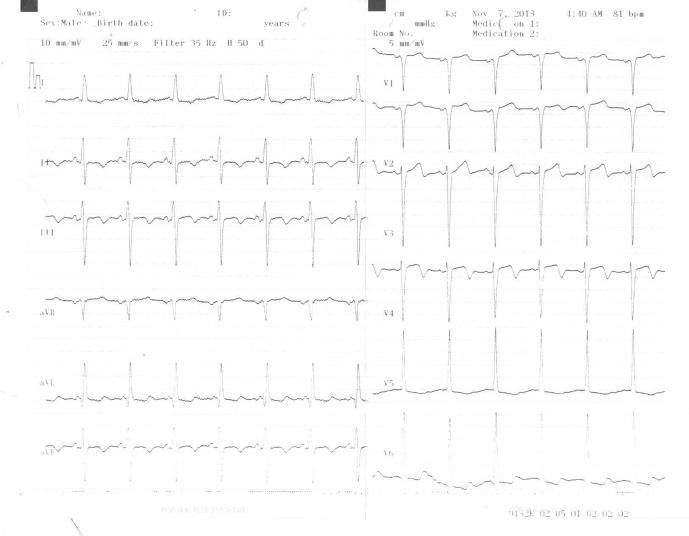

Myocardial bridge is defined as the narrowing of any coronary artery segment in systole but a normal diameter in diastole. It is most frequently seen on left anterior descending (LAD) artery. Left circumflex artery (LCx) is very rare. A 62 year-old male patient presented with severe, squeezing chest pain. The electrocardiogram showed T wave inversion in V1-V4 and ST depression in DII, DIII, aVF. Coronary angiography showed complicated lesion on after S2 branches of LAD and myocardial bridge causing 100% systolic narrowing of fourth obtus marginal branch of LCx. Bare metal stent was placed to LAD lesions with no residual occlusion. The patient was discharged with beta-blocker therapy. He had no recurrent chest pain during six months of follow-up.

心肌桥定义为任何冠状动脉节段在收缩期变窄而在舒张期直径正常。最常见于左前降支(LAD)动脉。左旋支动脉(LCx)非常罕见。一名62岁男性患者出现严重的压榨性胸痛。心电图显示V1-V4导联T波倒置,II、III、aVF导联ST段压低。冠状动脉造影显示LAD的S2分支后有复杂病变,心肌桥导致LCx的第四钝缘支在收缩期100%狭窄。对LAD病变置入裸金属支架,无残余闭塞。患者接受β受体阻滞剂治疗后出院。随访6个月期间无复发性胸痛。